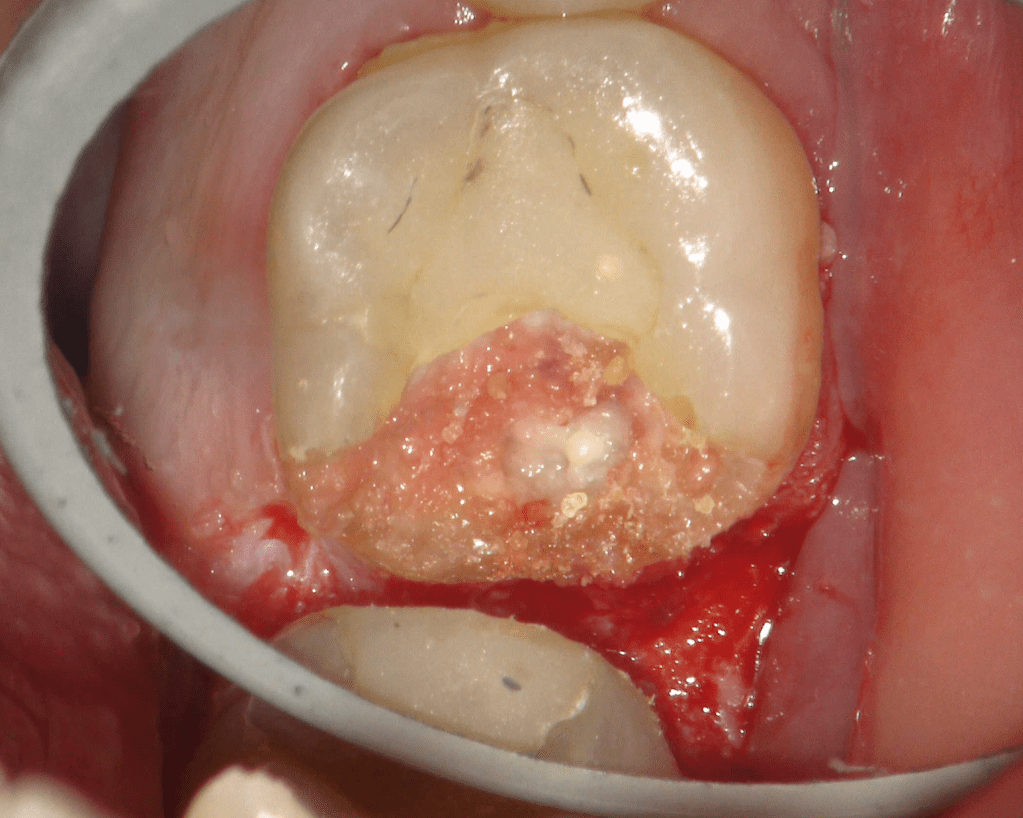

Reconstrucción preendodóntica

Molar superior

Reco preendo + 4 conductos molar superior

Reco preendo, 2o Molar superior